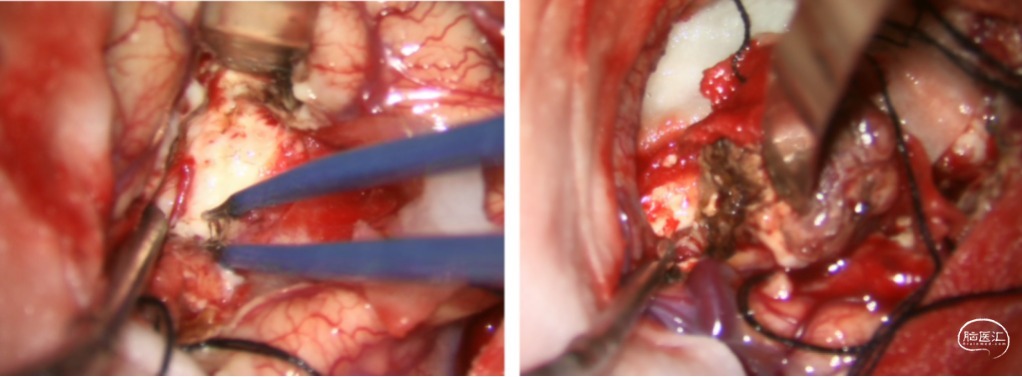

分离:沿边界分离畸形团,离断供血动脉;

切断:最后切断引流静脉,术区止血满意;